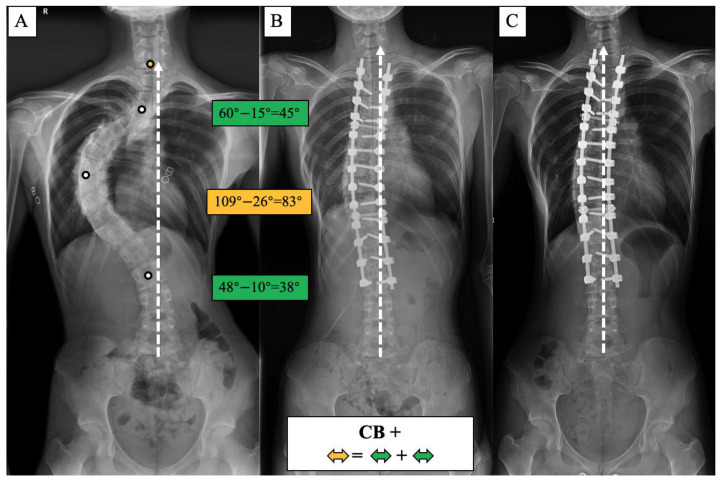

A surgical algorithm was proposed based on the CB classification to avoid postoperation CIB (Figure 3). In addition, a schematic diagram of the correction strategy for each type of patient is shown in Figure 4. For CB+ patients, the correction rate of the main curve (CRMC) should match the compensation curve. For CB− patients, the CRMC should match the compensatory curve. Most of the lumbar motion segments can be retained to provide optimal compensatory ability. However, the postoperative compensatory capacity of CB− patients is not as good as CB+ patients due to the limited mobility of the preserved lumbar motion segments. For CIB− patients, the CRMC should be greater than the compensatory curves. Osteotomy at the concave side of the main thoracolumbar curve is recommended. Multiple-level asymmetrical Ponte osteotomy is a safe and effective technique to improve the flexibility of the spine as well as the correction rate of rigid adult idiopathic scoliosis [ref. 15]. For CIB+ patients, the CRMC should be less than the compensatory curves, and the LIV should be kept even during the surgery. Preserving lumbar mobility is not the primary consideration when making a surgical plan for CIB+ patients. Typical cases are shown in Figure 5, Figure 6, Figure 7 and Figure 8.

The incidence of postoperative CIB was 50% in CB+ patients and 70% in CB− patients, which was the highest among the four groups. The majority of postoperative CIB in this case series was caused by a mismatch in the correction rate between the primary and compensation curves. Nearly half of the postoperative CIB was compensated to CB at the final follow-up, benefiting from the adjustment of the LIV inclination angle. The decompensation or CIB rate (CBD > 2cm) in the final follow-up was 28.26% and 40% in CB+ and CB− patients, respectively, higher than the 16.83% reported by Miller for 908 patients with AIS with a smaller preoperative Cobb angle of 60 degrees. To reduce the postoperative CIB, the correction rate of the main and compensatory curves should be consistent. Meanwhile, lumbar motion segments should be preserved as much as possible to provide the ability to spontaneously compensate. Bao et al. [ref. 22] reported that postoperative CIB with pelvic fixation may not compensate spontaneously during follow-up, resulting in permanent fixation decompensation.